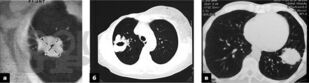

Учебное пособие основано на современных данных по диагностике и лечению рака легкого. Оно содержит информацию об эпидемиологии, этиологии, клинических проявлениях и профилактике заболевания.

В издании изложены сведения о современных методах исследования, применяемых для диагностики, оценки стадии заболевания с учетом Международной классификации по системе TNM и выбора оптимального метода лечения.